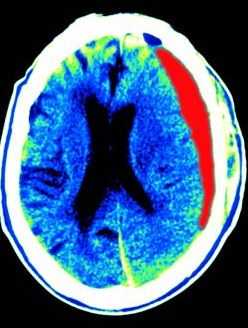

![субдуральная гематома]()

МРТ головного мозга. Т1-взвешенная аксиальная МРТ. Субдуральная гематома. Цветовая обработка изображения.